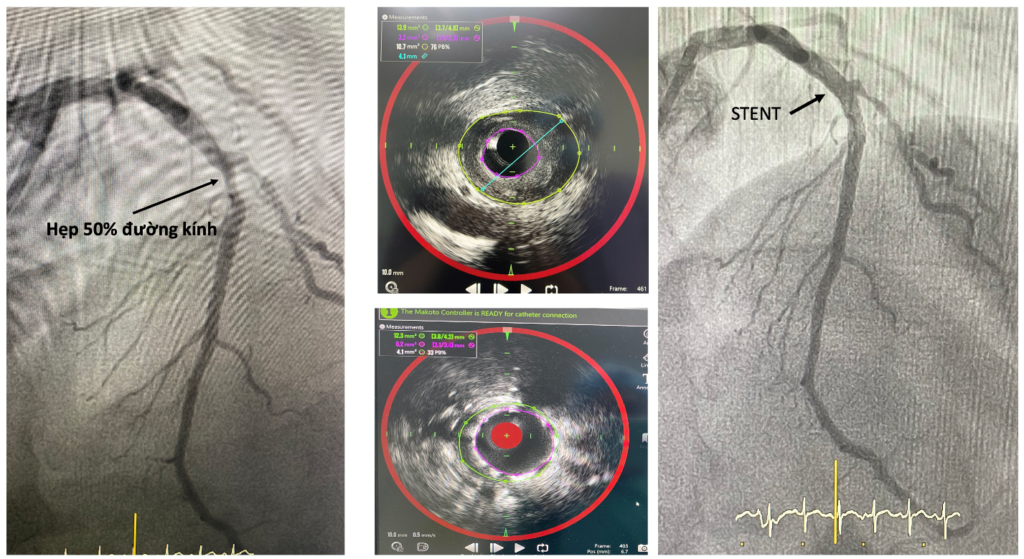

Hiệu quả của việc ứng dụng kỹ thuật NIRS–IVUS tại Bệnh viện Đa khoa Khánh Hòa được chứng minh qua các ca bệnh thực tế. Điển hình là bệnh nhân N.N.S. 65 tuổi, được chụp mạch vành ghi nhận hẹp khoảng 50% đoạn giữa nhánh liên thất trước. Tuy nhiên, khi tiến hành khảo sát sâu trong lòng mạch bằng NIRS–IVUS, kết quả cho thấy diện tích lòng mạch tại vị trí hẹp nhất chỉ còn 3,2 mm², trong khi mảng xơ vữa chiếm tới 76% diện tích lòng mạch và có thành phần giàu lipid. Đây là đặc điểm của mảng xơ vữa nguy cơ cao, dễ nứt vỡ và có thể gây biến cố tim mạch cấp. Trên cơ sở đánh giá toàn diện này, bệnh nhân được chỉ định can thiệp đặt stent.

Sau can thiệp, diện tích lòng mạch tại vị trí hẹp nhất tăng lên 8,2 mm², gánh nặng xơ vữa giảm còn 33%, cho thấy hiệu quả rõ rệt của việc đánh giá chính xác tổn thương và lựa chọn phương pháp điều trị phù hợp.